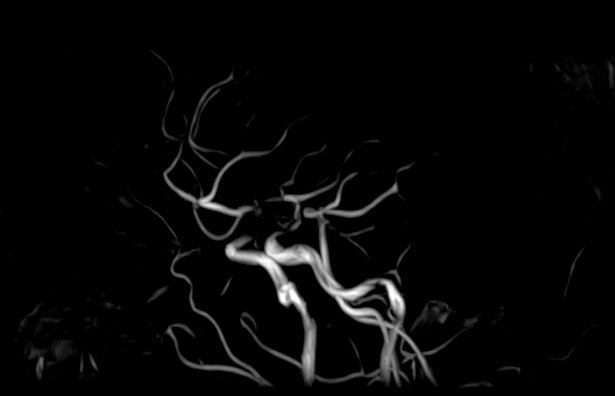

В клинике «Доступная медицина» проводится комплексное исследование: МР-ангиография шеи и головного мозга на новейшем высокопольном томографе экспертного уровня TOSHIBA VANTAGE TITAN 1,5 Тесла, который создает изображения сосудистой системы превосходного качества, что позволяет проводить точную диагностику и назначать пациенту своевременное лечение. МР-ангиография проводится в стандартном режиме без использования контраста.

- Суть исследования МРТ сосудов шеи и головного мозга

Суть исследования МРТ сосудов шеи и головного мозга

Для обнаружения заболеваний шеи, зачастую доктора назначают особые технологии проверки, например Доплер или рентген-анализ. Но бывают ситуации, связанные с вероятностью наличия в теле пациента аномальных процессов, происходящих в мягких тканях, тогда врачи выписывают направление на прохождение МРТ сосудов шеи. Подобное обследование показывает даже самые мелкие и незначительные изменения.